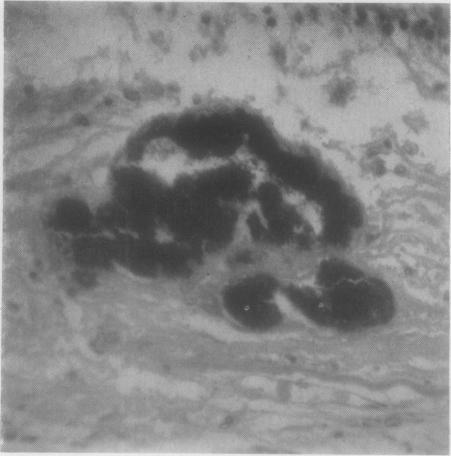

Fundus dystrophy with unusual features; a histological study.

Br J Ophthalmol. 1951 Dec;35(12):751-64. doi: 10.1136/bjo.35.12.751.